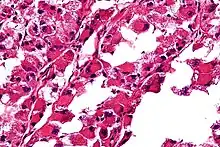

| Micrograph of an alveolar soft part sarcoma, showing the characteristic alveolar-like architecture and cells with eccentric nuclei and abundant eosinophilic cytoplasm. H&E stain. | |

The definitive diagnosis of ASPS is based on its appearance under the microscope (i.e., its histomorphology), and presence of the characteristic chromosomal translocation (i.e., cytogenetics).

ASPS' histomorphologic features include an alveolar-like pattern at low magnification and the presence of large cells with abundant eosinophilic cytoplasm and eccentric nuclei. Calcifications are commonly present, as may be seen with slow-growing neoplasms.